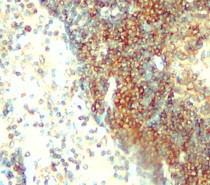

ARG66998 anti-ALIX antibody IHC-P image

Immunohistochemistry: Paraffin-embedded human colon cancer tissue stained with ARG66998 anti-ALIX antibody at 1:200 dilution. Antigen Retrieval: Boil tissue section in Citrate buffer (pH 6.0).